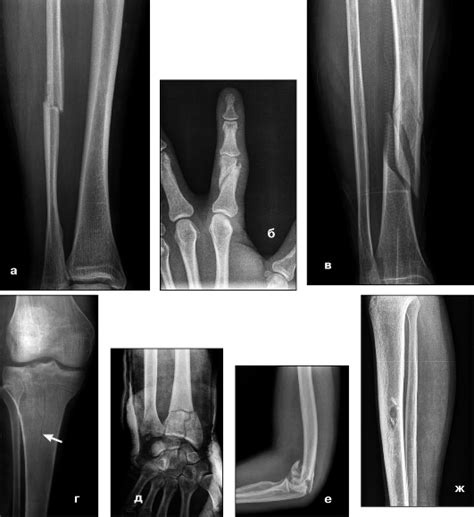

Виды переломов

Перелом | Портал радиологов

Какие бывают переломы. Первая помощь при перело...